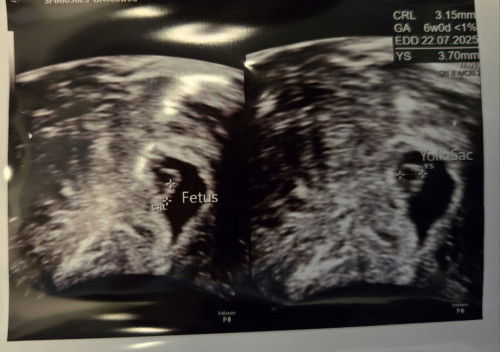

6 week scan: Comparing this pregnancy to my last pregnancy that ended in MC

I'm 36 and had a miscarriage when I was 32. We decided to try again in 2024. Here's a short comparison between this and my last pregnancy at 6 weeks. Compared to my last pregnancy, at 6 weeks I'm a lot more nauseous and have not had any bleeding. The last time I miscarried, i had bleeding and the fetus had a slow heart beat and my hcg was also low. I ended up mc at 10 weeks and had D&C at 11 weeks as it didn't come out. This time around, the fetus seems normal with Heartbeat at 130. Fetus at 3.15mm. I'm exactly 6 weeks from the 1st day of last period. And the baby is also 6 weeks old based on scan. However I think everyone is different and some may have a different gestational age on the scanning. Hoping everything goes well along with anyone else who had a miscarriage before :) and who is anxious about being older.